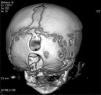

An encephalocele is a protrusion of the brain and/or meninges through a defect in the skull that is closed or covered with skin. Occipital encephaloceles are the most frequent type in North America and Western Europe, where about 85% of encephaloceles take this form. To the best of our knowledge, there are only three other reported cases of double occipital encephaloceles in the literature. The current study reports a double and both supra- and infra-torcular occipital encephalocele in a neonate and discusses the importance of preoperative neuroimaging studies to optimize the outcome. The patient was a 1-day-old male child who was identified by prenatal ultrasound to have two occipital encephaloceles. The patient underwent a closure of the occipital encephalocele on the second postnatal day. The infant tolerated the procedure well and was extubated on the first postoperative day. The child continues to do well during follow-up.